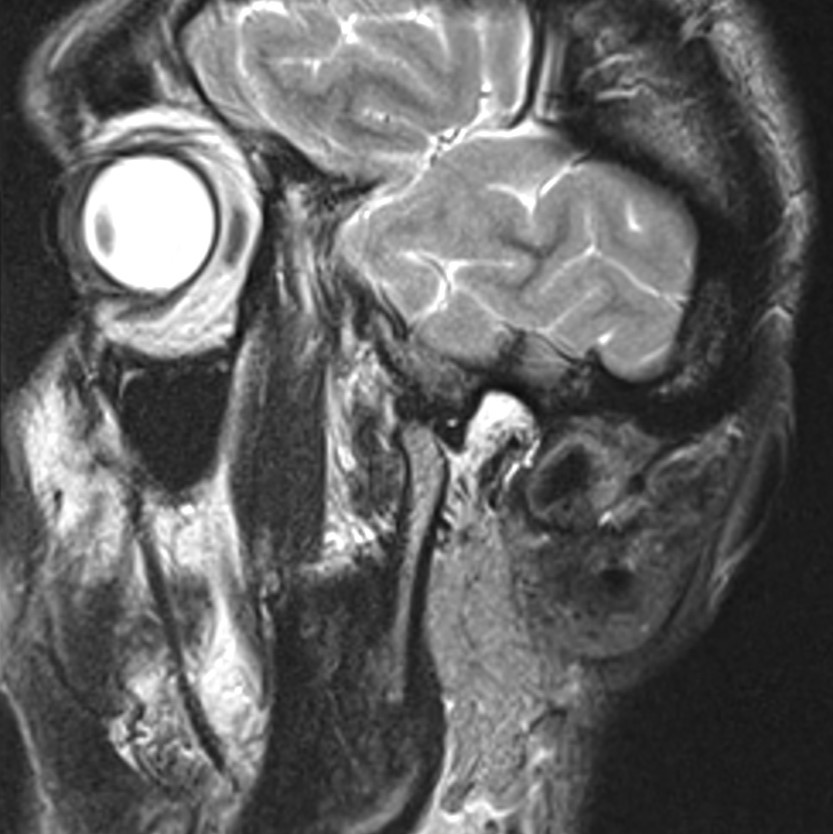

Височно-нижнечелюстной сустав является парным комбинированным суставом и имеет сложное строение. В него входят суставные ямки височной кости, суставные головки нижней челюсти и расположенные между ними хрящевые пластинки – мениски, выполняющие роль амортизаторов.

Чаще всего дисфункция височно-нижнечелюстного сустава обусловлена внутренним повреждением, смещением мениска и суставной головки нижней челюсти. Для определения степени смещения внутрисуставных структур выполняется функциональная проба с проведением МРТ в двух положениях:

Магнитно-резонансная томография является наиболее точным и эффективным методом диагностики поражения височно-нижнечелюстных суставов, так как позволяет получить детальную информацию о состоянии не только костей, но и связочного аппарата, хрящей, менисков, жевательных мышц, окружающих мягких тканей.

При проведении магнитно-резонансной томографии на изображениях визуализируются: височная кость, головка мыщелкового отростка нижней челюсти, суставная щель. Помимо костных структур МРТ позволяет оценить состояние мягких тканей – внутрисуставного диска и связочного аппарата височно-нижнечелюстного сустава, жевательных мышц.